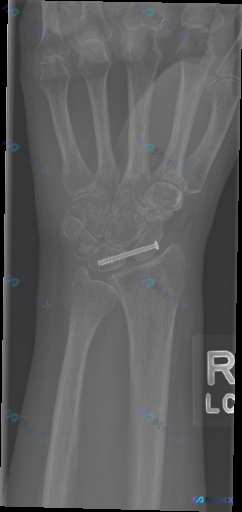

右腕舟骨内固定术后正位片:看似恢复尚可,这张片子真的没问题吗?

病例背景:成年人,右腕舟骨骨折术后复查,本次先提供右侧手腕正位X光片。

- 腕部中央可见一枚内固定螺钉,横贯舟骨腰部,提示舟骨骨折手术史

- 桡骨远端、尺骨茎突及其余腕骨、掌骨基底部,未见明显新鲜骨折线或脱位征象

- 桡腕关节、下尺桡关节间隙在生理范围内,腕骨排列弧度基本自然

- 整体骨小梁结构尚可,未见明显弥漫性骨质疏松或病理性骨质破坏

- 未见明显局部软组织肿胀,金属异物为医疗植入物

- 骨骺线已闭合,符合成年人骨骼发育特征

目前正位片上没有看到明显的螺钉松动、断裂,也没有明显的急性骨破坏或脱位,但结合术后随访的场景,总觉得需要更谨慎地判断。

📋答案:结合临床背景与影像特点,最需要优先警惕的异常方向是「舟骨近端缺血性坏死(AVN)或隐匿性不连」。